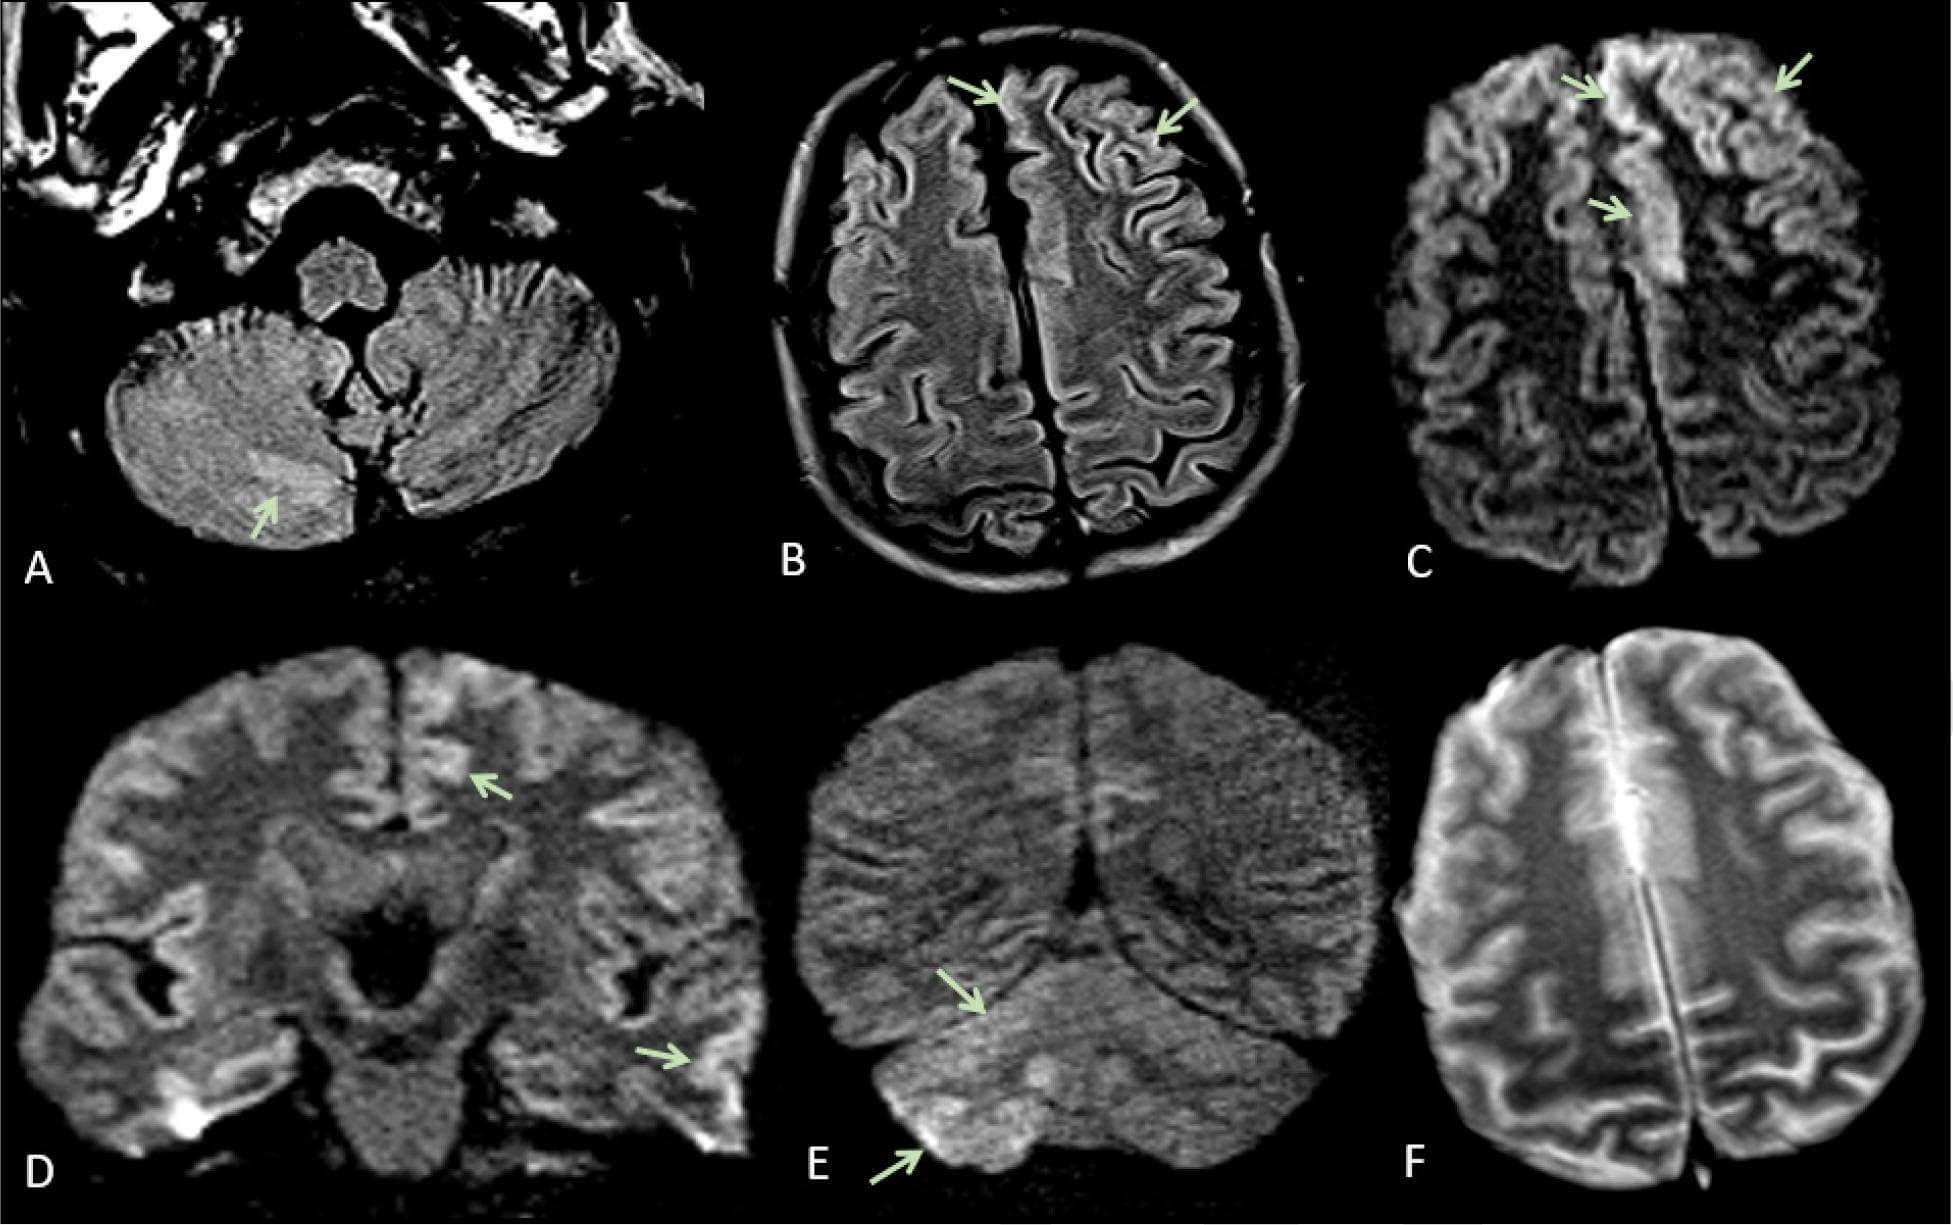

МРТ-снимки мозга пациента с подтвержденным COVID-19.

Результаты еще одного исследования также заставляют содрогнуться – проанализировав мозговую ткань восьми пациентов, умерших от COVID-19 исследователи увидели сходство с мозгом людей, которые умерли от нейродегенеративных заболеваний, таких как болезнь Альцгеймера и Паркинсона.

«Мозг пациентов, умерших от тяжелого COVID-19, показал глубокие молекулярные маркеры воспаления, хотя у этих пациентов не было никаких клинических признаков неврологических нарушений», – слова соавтора исследования Тони Висс-Корай, профессора неврологии и неврологических наук в Стэнфордском университете приводит medicalexpress.

В ходе работы команда проанализировала мозговую ткань восьми человек, умерших от COVID-19, и 14 человек, умерших от других причин. Хотя в мозге умерших пациентов с COVID-19 наблюдалось значительное воспаление, в их мозговой ткани не было никаких признаков SARS-CoV-2, вируса, вызывающего COVID-19.

Авторы исследования также отмечают, что у многих пациентов с COVID-19, особенно у тех, кто столкнулся с неврологическими проблемами или у тех, кто госпитализирован, присутствуют нейровоспалительные маркеры, которые наблюдались у умерших от болезни

«Вирусная инфекция, по-видимому, вызывает воспалительные реакции во всем организме. Они, в свою очередь, могут спровоцировать нейровоспаление в мозге», – пишут исследователи.

Авторы научной работы также отмечают, что полученные результаты помогу объяснить многие неврологические и психиатрические симптомы, которые наблюдаются у пациентов с длительным ковидом. Работа опубликована в журнале Nature, в ней также говорится, что ученые расходятся во мнениях о том, присутствует ли вирус в мозге пациентов с COVID-19.